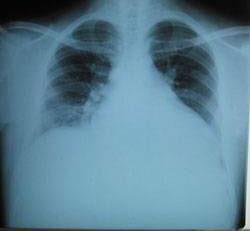

摘要:關(guān)于擴張性心肌病的最新治療,小巷深處的隱藏寶藏正逐漸為人們所發(fā)現(xiàn)。通過先進的醫(yī)療技術(shù)和方法,擴張性心肌病的治療取得了新的進展。這些治療方法旨在改善心臟功能,提高患者生活質(zhì)量。小巷深處的醫(yī)療機構(gòu)或?qū)<铱赡茈[藏著寶貴的治療經(jīng)驗和方法,為尋求最佳治療方案的病患帶來希望。更多詳細信息需要進一步探索和研究。

擴張性心肌病是一種嚴重的心臟疾病,但“心之港灣”為你帶來希望,這里的專家團隊一直在深入研究擴張性心肌病的最新治療方法,并深知每位患者都渴望得到最佳的治療和關(guān)懷,他們努力不懈,為患者帶來生機和新生。

你將了解到最新的藥物治療、心臟康復(fù)計劃以及生活方式調(diào)整等方面的知識?!靶闹蹫场边€開展了一系列臨床試驗,為患者提供最新的治療方案,他們的治療方法全面且個性化,因為每個患者的狀況都是獨特的,所以需要因人而異定制治療方案。